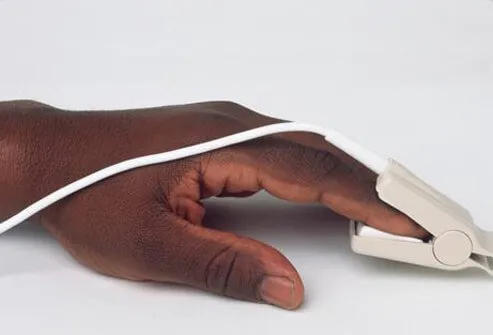

COPD診斷的一個重要部分是體格檢查,患者的呼吸史、吸煙史和COPD家族史。執行的第一個簡單的非侵入性測試通常使用脈搏血氧儀(如本幻燈片的圖片所示)。血氧儀測量血液中的氧氣量(飽和度百分比)。這是一種測試有多少氧氣被輸送到離心臟最遠的身體部位(例如手臂和腿)的方法。脈搏血氧計放置在身體部位(手指、耳垂)上,使用光來測量氧氣水平。